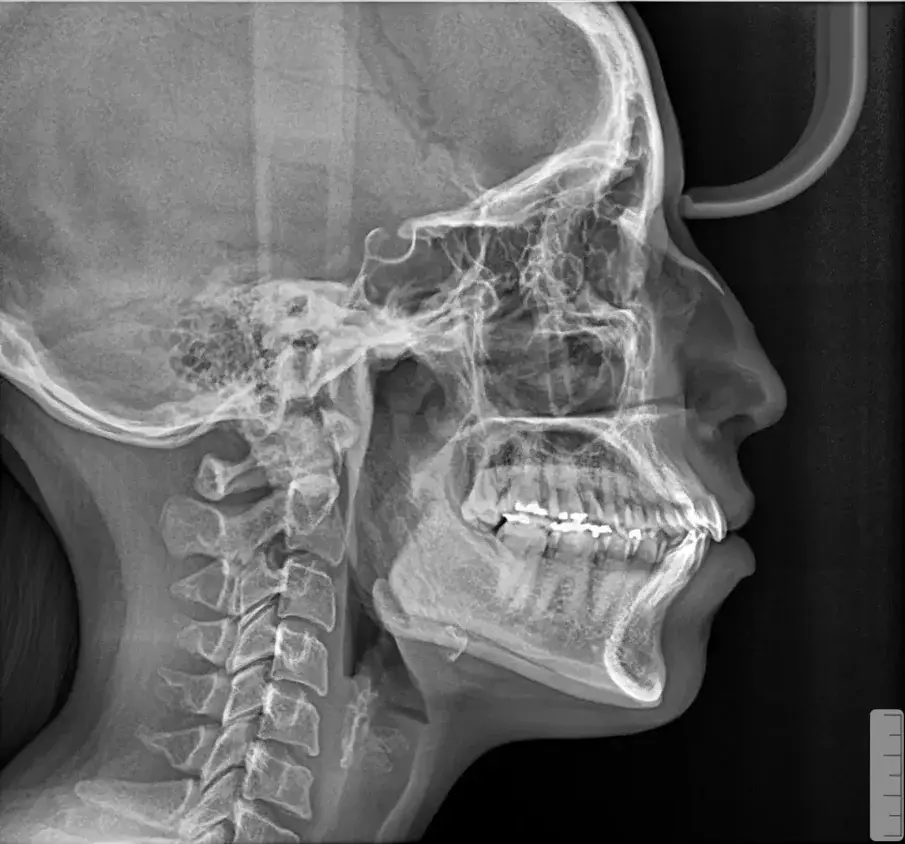

Фиг. 4а.

Първоначална цефалометрична рентгенография и панорамна дентална томография.

Фиг. 4b.